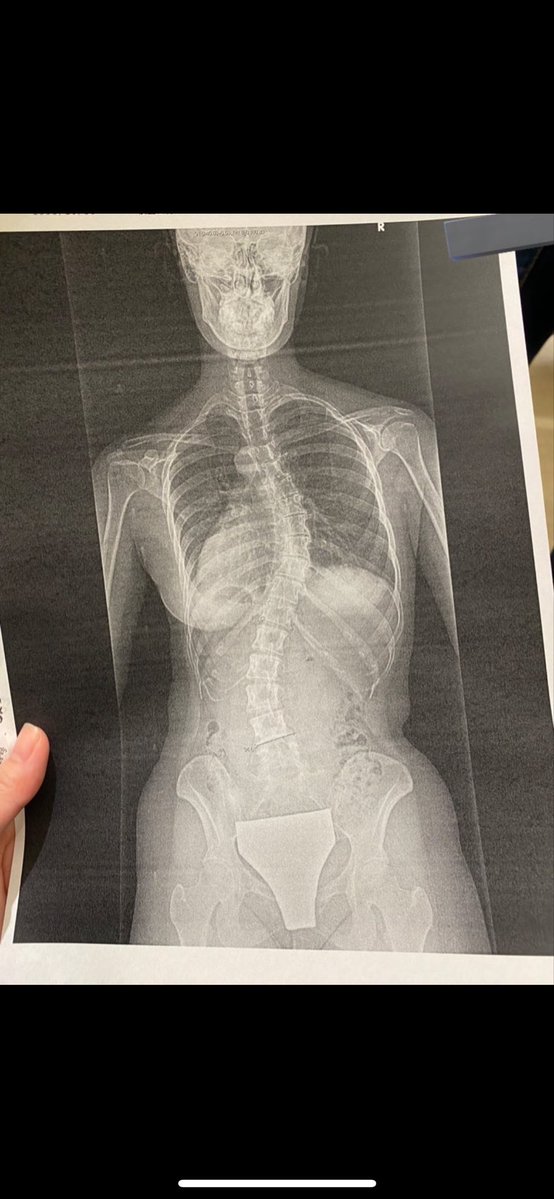

うちのよっめも酷く背骨捻れてたけど、整体で直った。 ゴットハンドの先生天国に行ってしまったけどね。